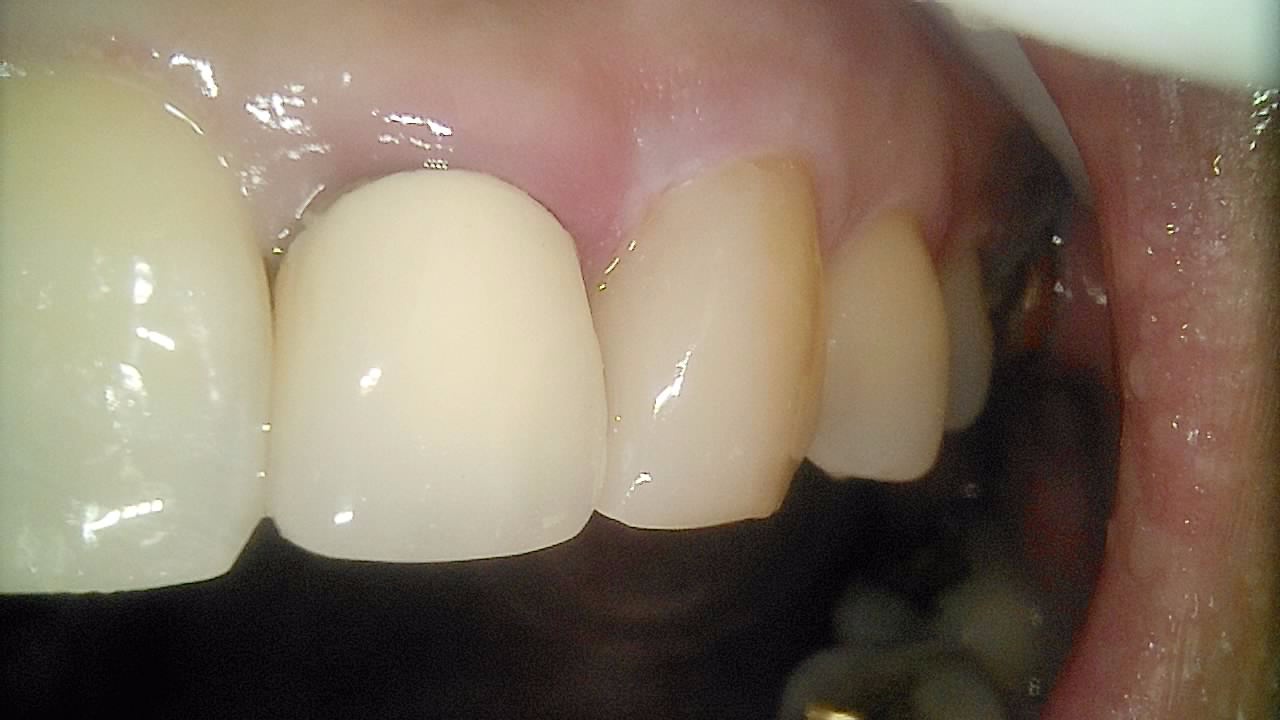

일반진료

BEFORE & AFTER